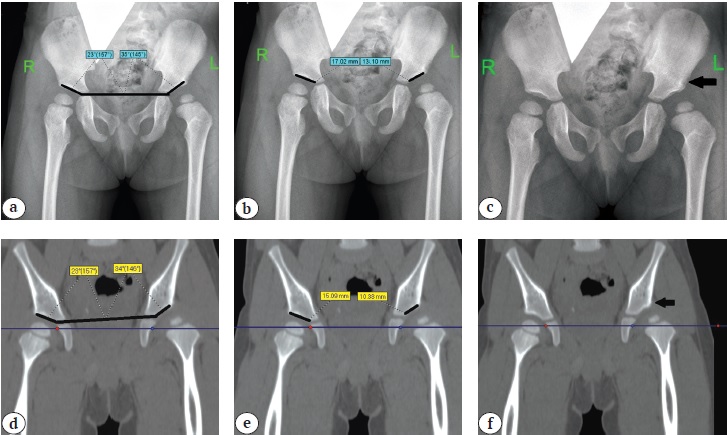

In order to objectify the data, the above-mentioned criteria were calculated using both X-rays and CT slice in the middle of the acetabulum (Figs. 1, 2).

Fig. 1. Determination in patients with Tönnis grade II DDH based on X-ray and CT results: a, d — acetabular index; b, e — extent of acetabulum arch (length of the sclerosis zone); c, f — presence of bone oriel (indicated by black arrow)